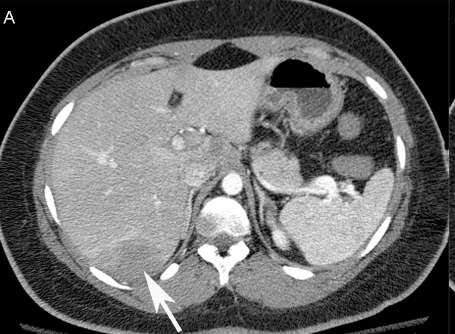

SIRT 在技术上的考虑首先要了解动脉解剖,采用微导管,使用使用高压注射器 另外要考虑Cone Beam CT的使用 6个月后,完全缓解 肝转移癌 增强CT Cone Beam CT

6个月后,完全缓解

肝转移癌

增强CT